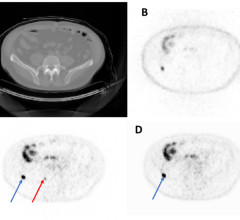

June 24, 2023 — A newly developed technology called “augmented whole-body scanning via magnifying PET” (AWSM-PET) has ...